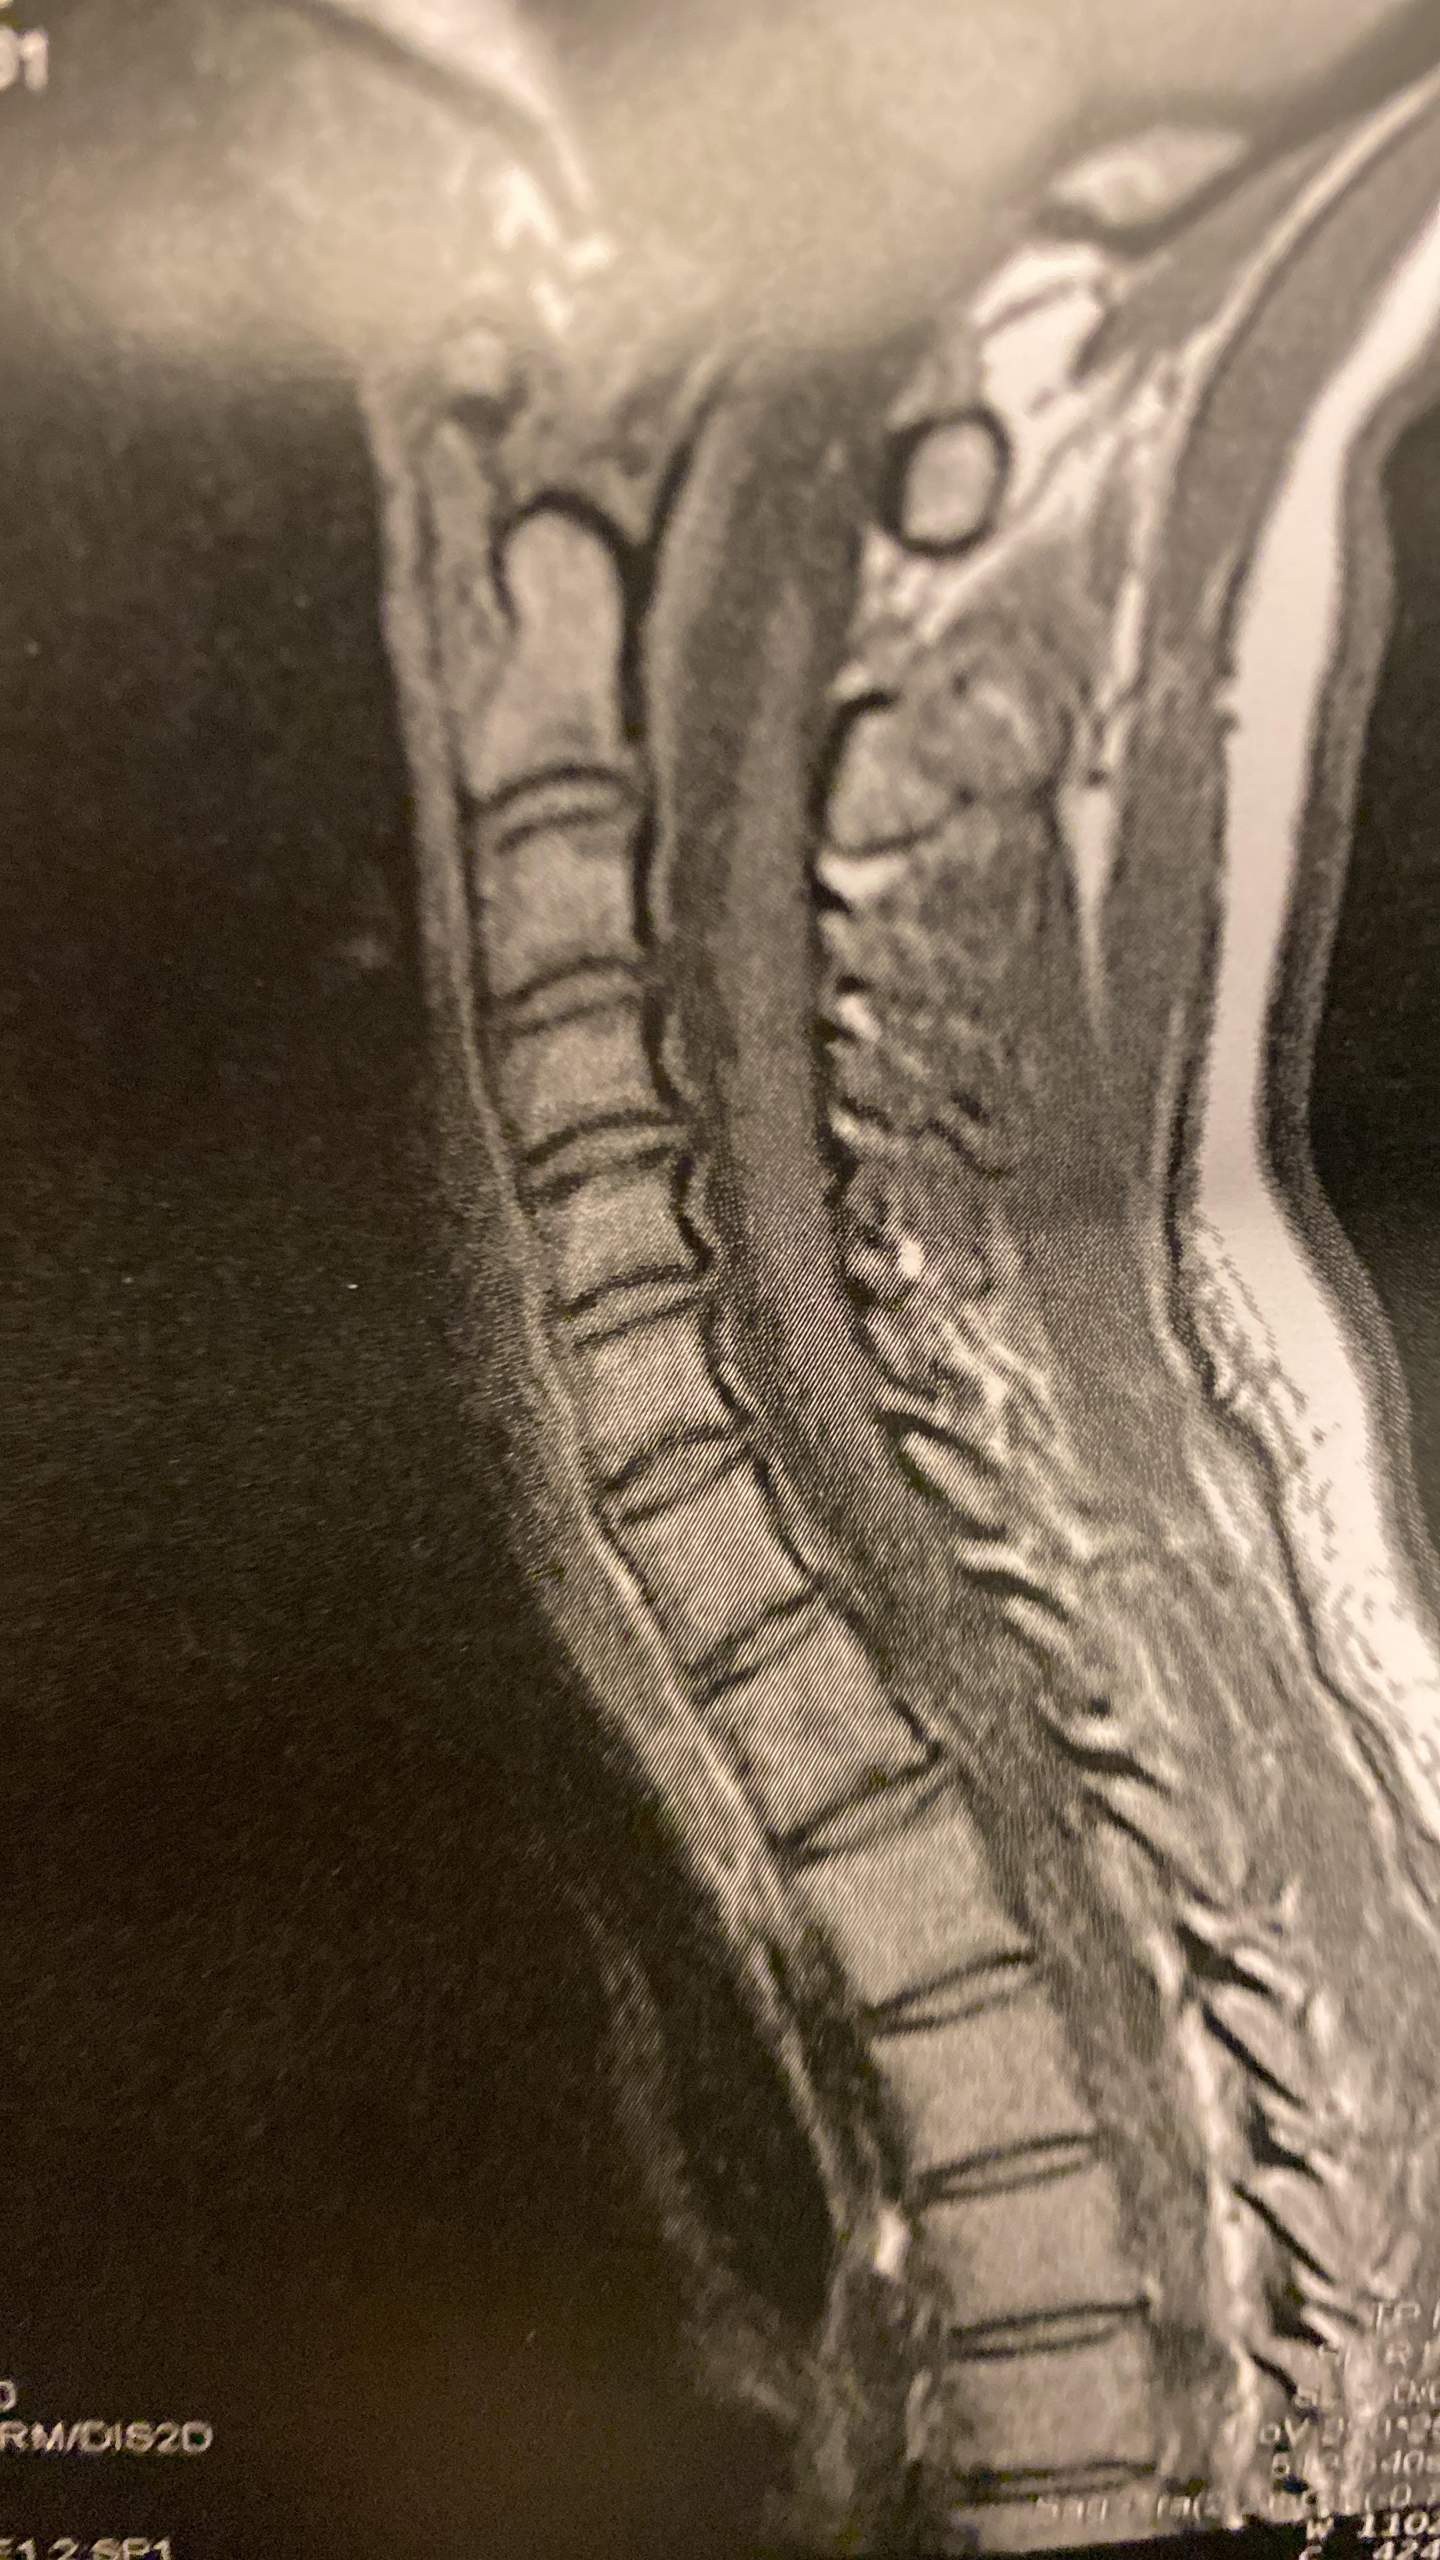

Übung 2: Mobilisationsübung. nach unten herausgeschoben. Vor allem andauernde Fehlhaltungen, zum Beispiel bei sitzender beruflicher Tätigkeit, sind verantwortlich.Symptome bei einem Bandscheibenvorfall der HWS: heftige Schmerzen im Bereich von Nacken und Hals. Kurzübersicht. Nach einer Operation an der Lendenwirbelsäule (LWS), wie einer Bandscheiben-Operation oder einer Stenose-OP, ist die Wiederaufnahme der Arbeit meistens 6 bis 12 Wochen nach der Entlassung möglich. 3 Tage Arcoxia eingenommen, dann wegen mässigem Erfolg abgesetzt.Was ist eine HWS-OP? Ziel einer Operation im Bereich der Halswirbelsäule ist es, durch einen Bandscheibenvorfall entstandene Schmerzen und Bewegungseinschränkungen beim Patienten zu beheben. Wenn die ausgetretene Bandscheibe auf einen Nerv drückt, können zudem weitere Symptome hinzukommen: Kribbeln oder Gefühlsstörungen . Durch diese Übung wird die Beweglichkeit der LWS gefördert.Nach einem Bandscheibenvorfall an der LWS kann es eine lange Reise zur vollständigen Genesung geben.Tätigkeit: Medizinredakteurin Der Orthopäde diagnostiziert mittels Computer-Tomografie (CT) oder Magnet-Resonanz-Tomografie (MRT) den Bandscheibenvorfall. An der Lendenwirbelsäule kommen mehr als 90 Prozent aller Bandscheibenvorfälle vor.

Bandscheibenvorfall HWS. Bei plötzlich auftretenden Schmerzen im . Kraftausfälle, wie z. Das passiert bei einem Bandscheibenvorfall. angespannter Nackenmuskulatur. einer steifen Kopf- und Halshaltung. Wann braucht man ein MRT der HWS? EMG (Elektromyographie) Wirbelsäulenvermessung.

Ein Bandscheibenvorfall kann in der Lendenwirbelsäule (LWS), Halswirbelsäule (HWS) oder in ganz seltenen Fällen in der Brustwirbelsäule (BWS) vorkommen. In etwa 90 Prozent der Fälle tritt ein Bandscheibenvorfall im Bereich der Lendenwirbelsäule (LWS) auf.Bei einem Bandscheibenvorfall an der Halswirbelsäule sind folgende Symptome typisch: Nackensteife und Nackenschmerzen (Schulter-Nacken-Schmerz) Ausstrahlende Schmerzen in Kopf, Arm, Hand und .Bandscheibenvorfall an der Halswirbelsäule (HWS) Wenn ein Bandscheibenvorfall an der Halswirbelsäule (kurz HWS) Symptome auslöst, äußern sich diese oft in Form von . Weitere Symptome können Taubheitsgefühle, Kribbeln und Schwäche im Arm oder der Hand sein. Aufbau und Funktion der Bandscheiben. Ursachen und Risikofaktoren.deBandscheibenvorwölbung der HWS – So gefährlich kann . Ein Bandscheibenvorfall der Halswirbelsäule, auch zervikaler Bandscheibenvorfall oder zervikale Diskushernie, ist eine häufige Erkrankung, die bereits ab dem mittleren Lebensalter auftreten kann. Sie verursachen über die Jahre Veränderungen an den Wirbelgelenken, . Verlauf und Prognose. Wenn er zu einer Operation rät, stehen zwei unterschiedliche Methoden zur Verfügung: Schlüsselloch-Operationen, also minimal-invasive Chirurgie. Abnutzung, Elastizitätsverlust und Risse im Faserring der Bandscheibe sind die Ursachen. Der gallertige Kern kann sich aber dadurch nach außen wölben und ein Engpass bewirken. Diese HWS Operation unter Vollnarkose erfolgt im Normalfall von vorn (ventral) über einen querverlaufenden, etwa 5 Zentimeter langen Hautschnitt. Fehlempfindungen wie Taubheitsgefühl, gestörtes Temperaturempfinden.Zu den bandscheibenbedingten Wirbelsäulenerkrankungen zählen. Fachlich geprüft von Dr. Inhalte im Überblick.